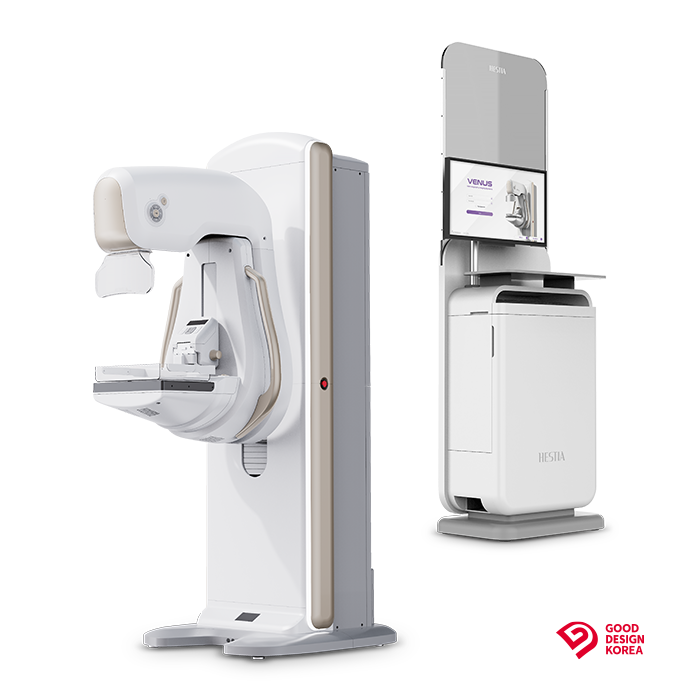

Mammograf HESTIA

Poznaj mammograf Hestia – zaawansowane technologicznie rozwiązanie stworzone z myślą o najwyższych standardach diagnostyki obrazowej. To połączenie wyjątkowej jakości obrazu, ergonomii pracy i troski o komfort pacjentki.

Zaprojektowany z myślą o codziennej pracy w szpitalach i centrach diagnostycznych, mammograf Hestia to nie tylko urządzenie – to inwestycja w pewność, bezpieczeństwo i zaufanie.

Chcesz dowiedzieć się, co wyróżnia Hestię na tle innych mammografów? Przejdź dalej i odkryj kluczowe funkcje, które zmieniają jakość badań piersi.